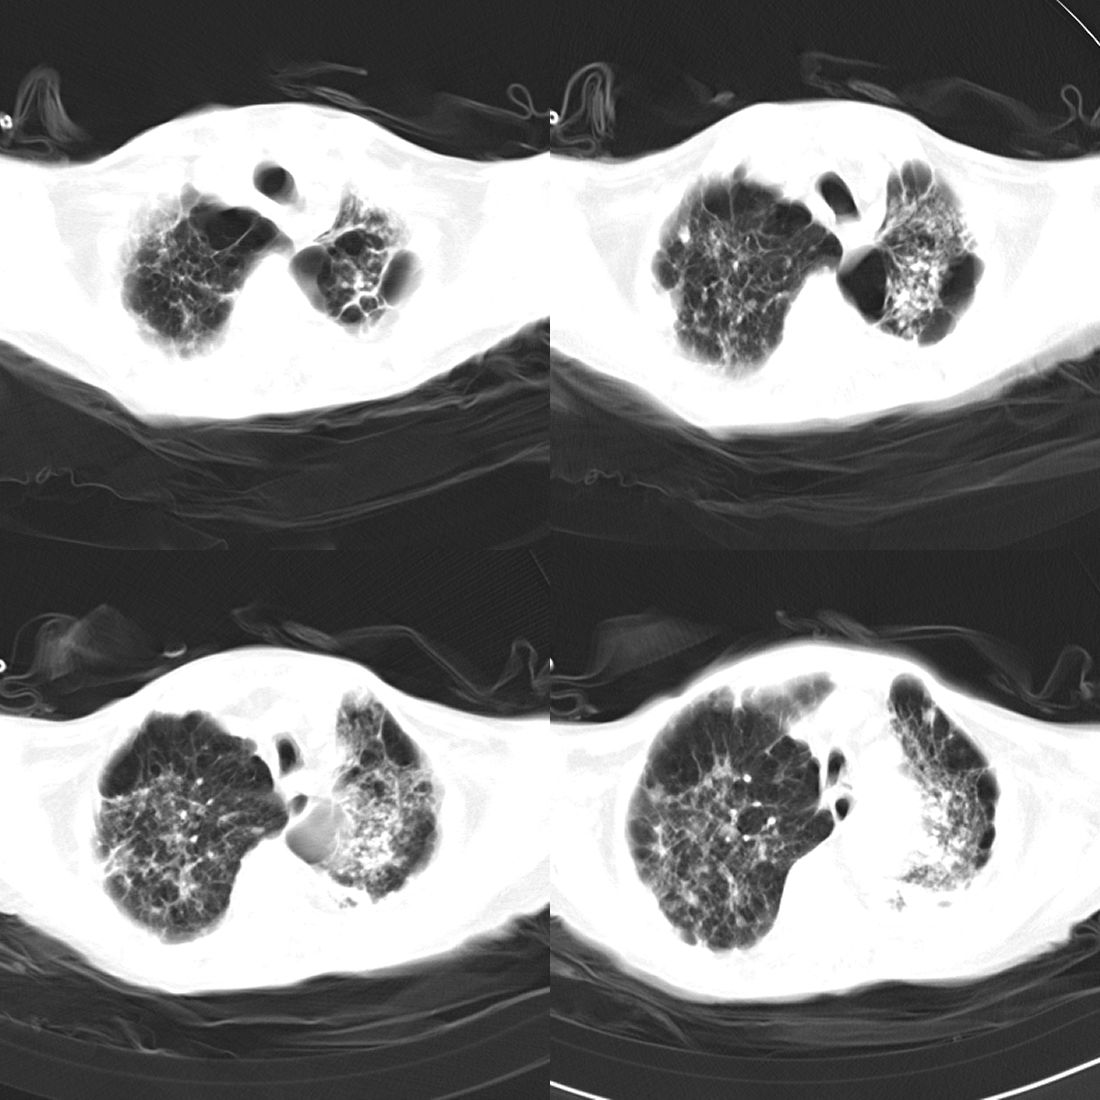

以下是引用zsl6918在2008-11-29 21:51:00的发言:[br]建议追问病史有无粉尘接触史,鉴别是结核还是矽肺。另外,左侧肺门的改变需强化明确,除外占位。

以下是引用liuyue在2008-11-30 6:01:00的发言:[br]双肺继发性肺结核;左侧包裹性积液;建议增强化或支气管镜检查除外左肺占位性病变.